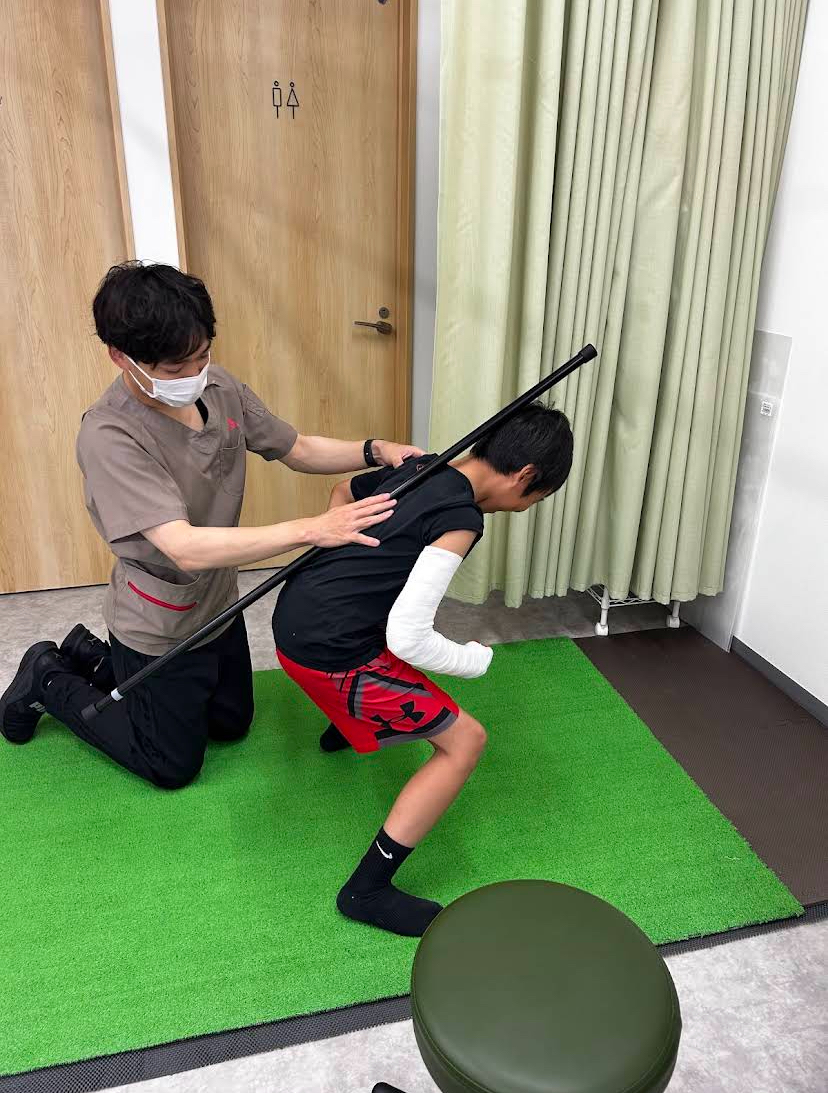

早期復帰は、固定+リハビリ

掌側板損傷は、初期は

-

過伸展を防ぐ固定

-

ギプスに近い固定(ルナキャスト固定)

その後

-

関節可動域の回復

-

組織回復の超音波治療機器

-

競技復帰へのステップ

を見ながらリハビリを進めていきます。